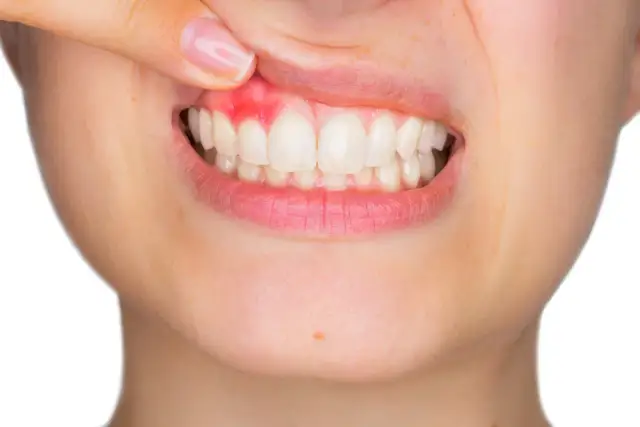

- Zmiana koloru dziąseł mogą stać się zaczerwienione, obrzęknięte lub cieńsze.

- Krwawienie dziąseł zauważalne podczas codziennego szczotkowania lub nitkowania zębów.

Choroby przyzębia, a w szczególności paradontoza, to jedna z głównych przyczyn recesji dziąseł. Paradontoza to przewlekła infekcja bakteryjna, która prowadzi do stanu zapalnego dziąseł, a następnie do destrukcji tkanek otaczających ząb, w tym kości szczęki. Postępujący stan zapalny osłabia tkanki dziąsłowe, powodując ich zanik i odsłonięcie szyjek zębowych. Leczenie paradontozy jest absolutnie kluczowe, aby zatrzymać postęp recesji i uratować zęby przed utratą.